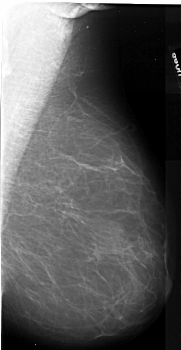

A_1083_1.LEFT_MLO

LEFT_MLO LINES 6286 PIXELS_PER_LINE 3571 BITS_PER_PIXEL 16 RESOLUTION 42 OVERLAY